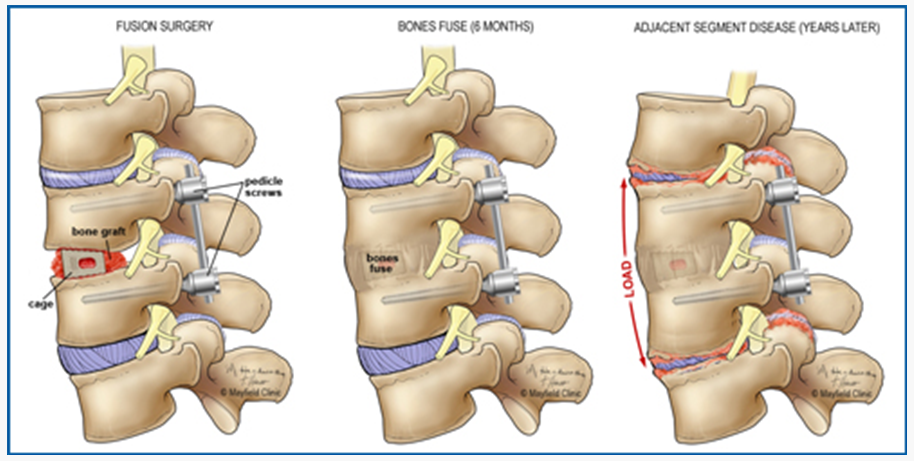

그러나, 유합술이 되어있는 상태에서는 해당 유합술 인접부에 문제가 생기는 경우가 흔하다.

Adjacent segement disease (인접분절 질환) 이라고

불리는 것인데,

척추 유합술을 하고 난 이후

원래는 골고루 분산되던 힘이 유합술로 인해 분산이 이루어지지 않으며

위, 아래 쪽의 척추 및 디스크, 신경이 나오는 길 쪽으로 퇴행성 변화 등을 일으키는 것이다.

이로 인해 협착증이나 디스크 증상이 나타날 수 있다.

예상대로, 6-7번 유합술 된 주변,

C4-5, C5-6, C7-C8 사이로

디스크 탈출 및 퇴행성 변화, 협착 등

인접분절 질환을 보여주는 양상을 확인할 수 있다.